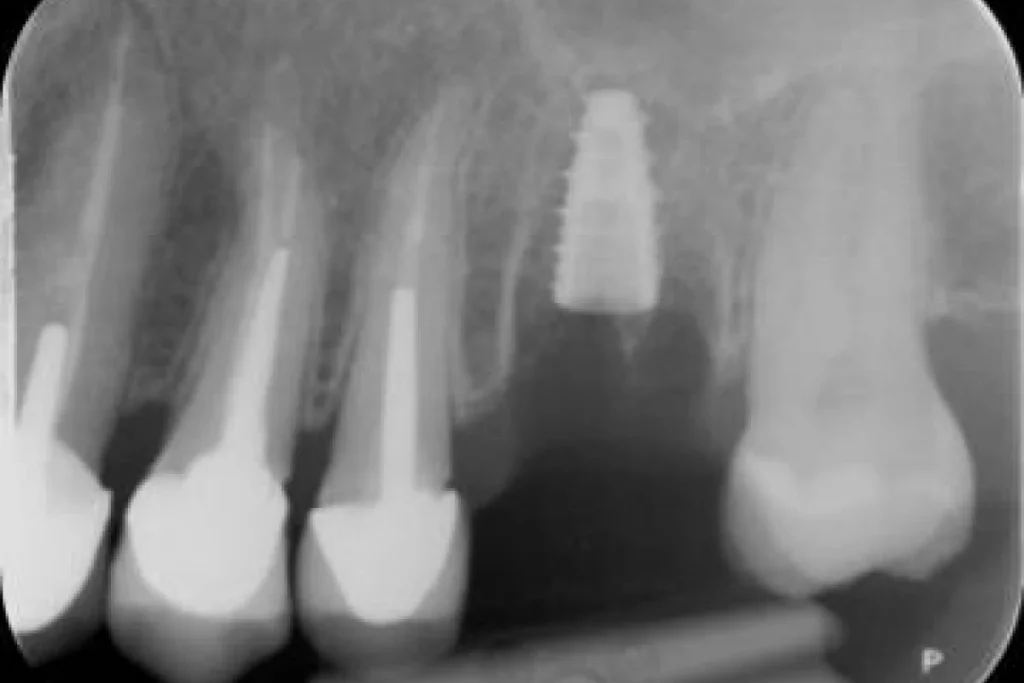

Mr C. 40 ans vient nous consulter pour une visite de routine. L’examen clinique et met en évidence un infection sous une dent couronnée il y plusieurs années par un confrère. Le scanner réalisé au cabinet confirme la nécessité d’extraire cette dent et nous décidons de réaliser un protocole d’extraction implantation et mise en esthétique immédiate.

En clair, nous réalisons l’extraction de la dent, la mise en place de la racine artificielle ou implant et la fabrication d’une couronne provisoire en résine le tout lors de la même séance. Le patient repart du cabinet avec toutes ses dents!